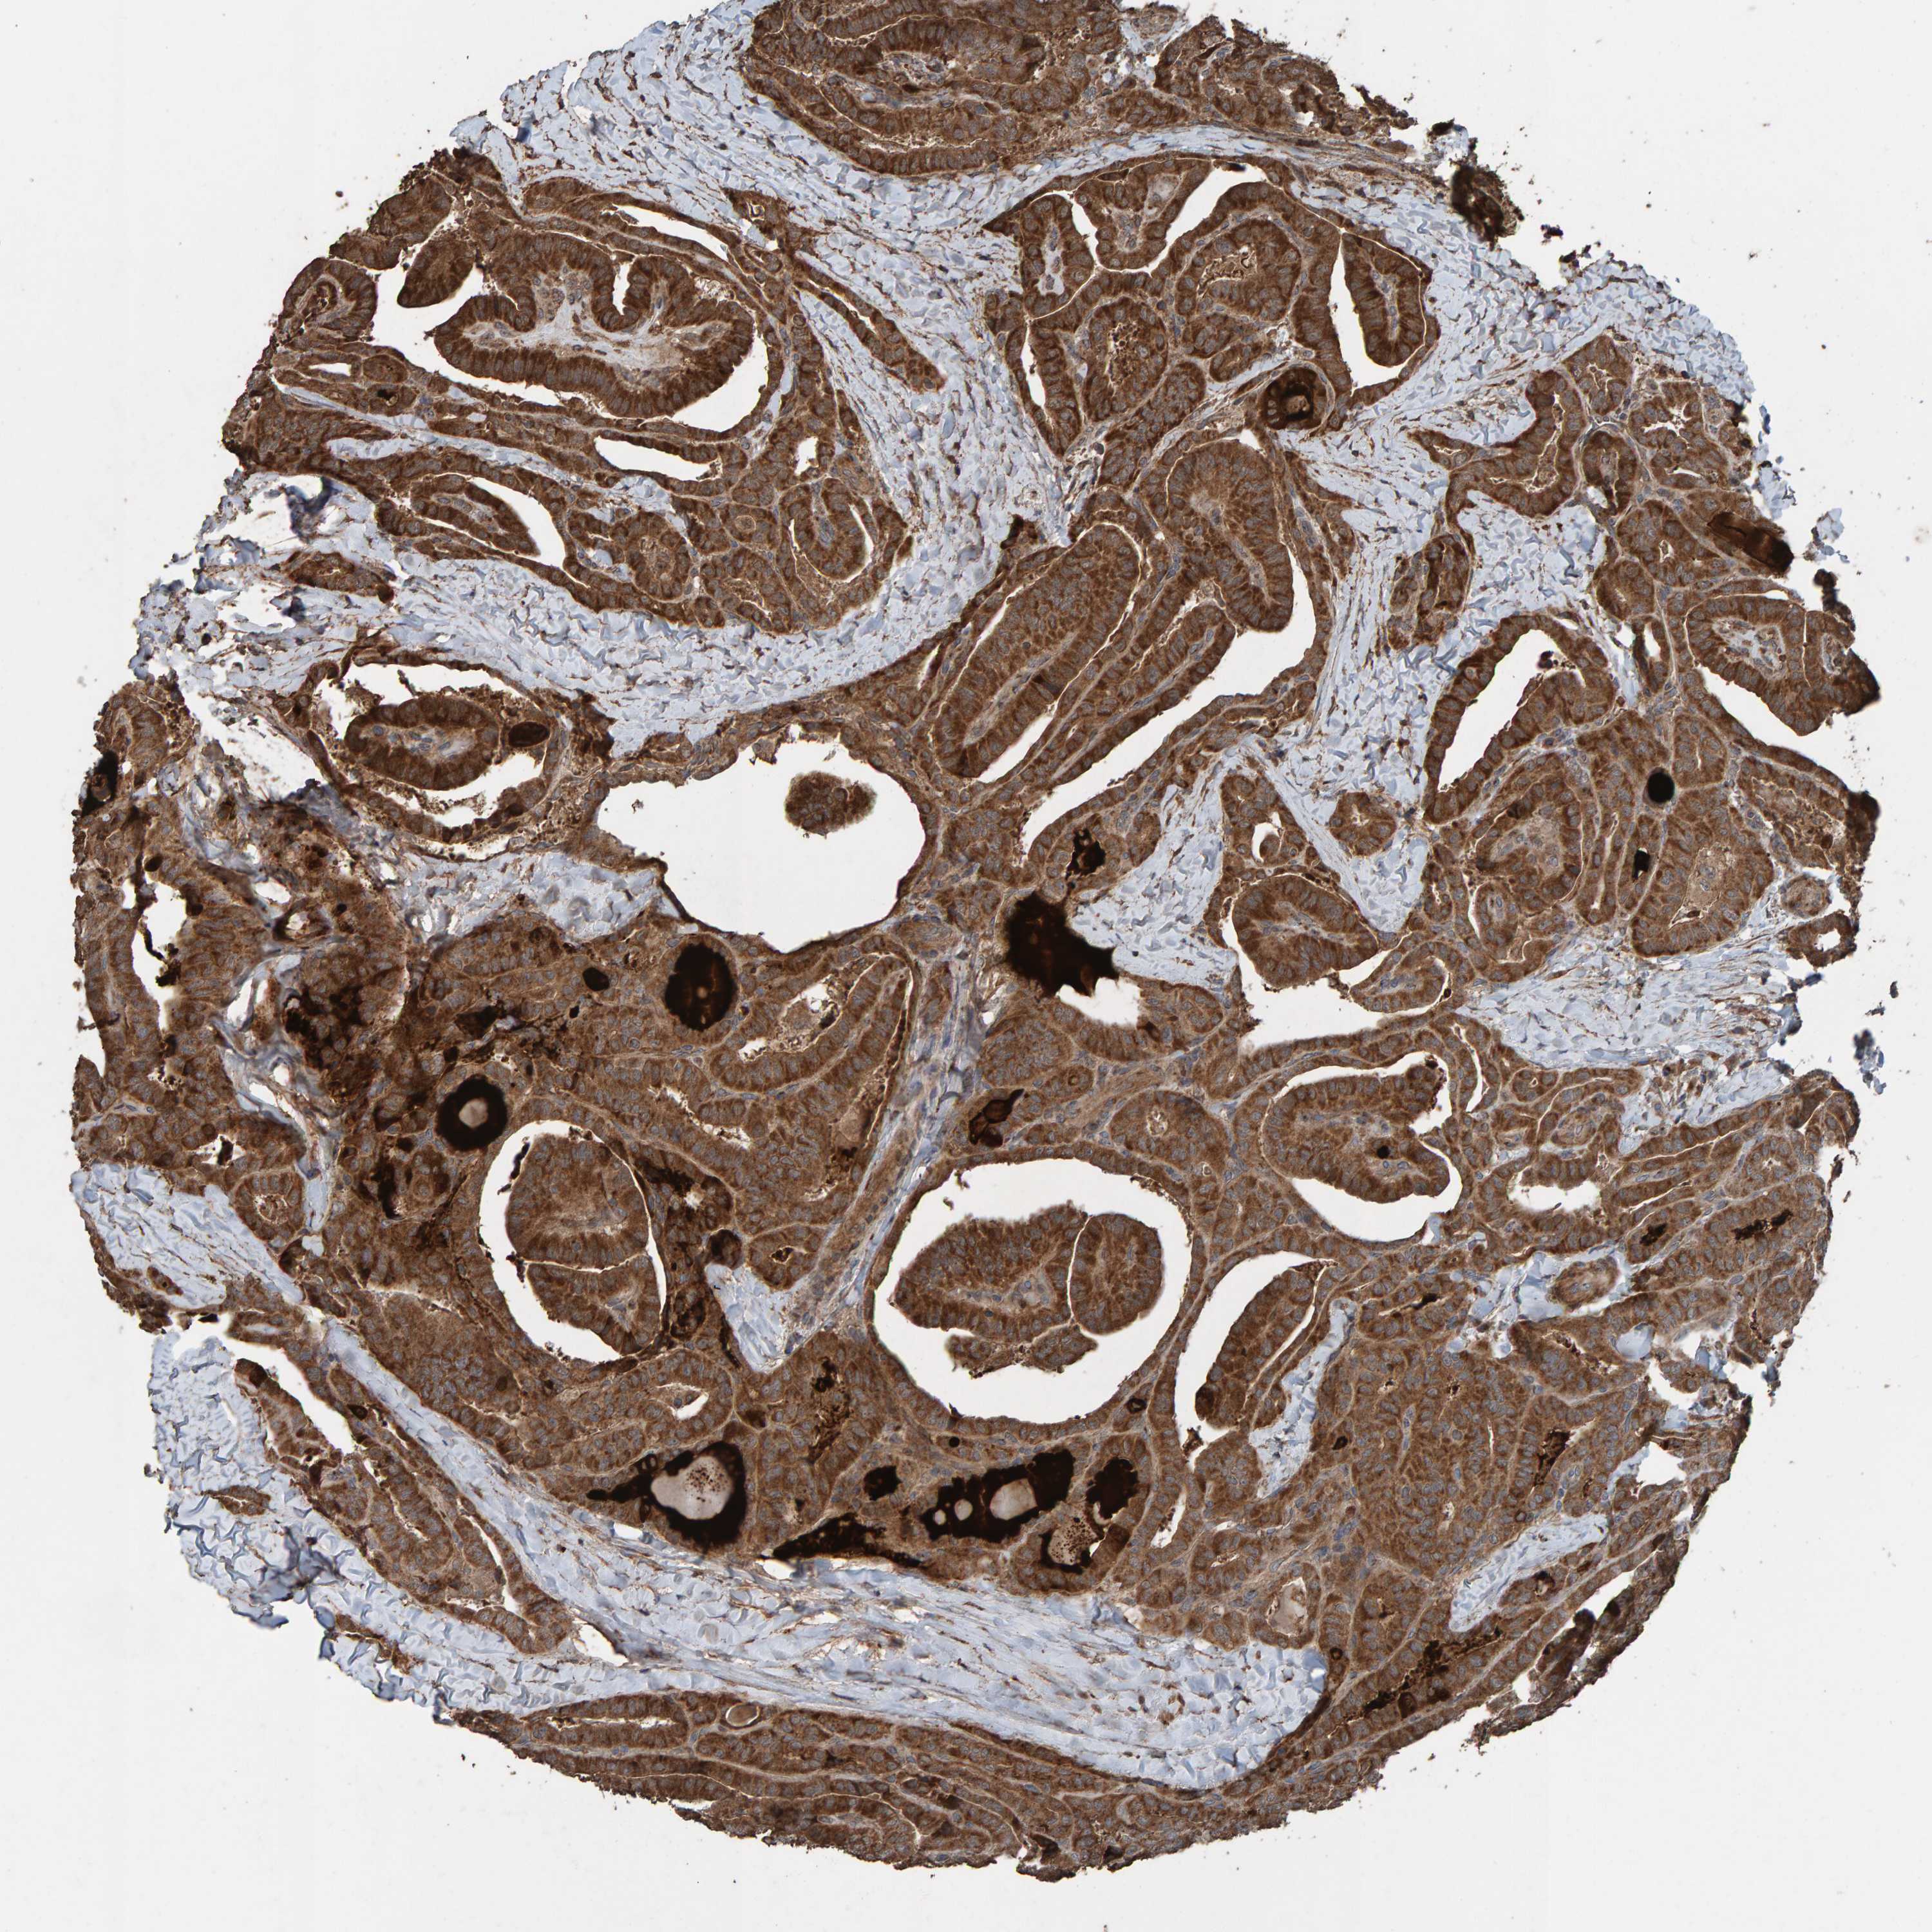

THYROID CANCER - Protein expressioni

A mouse-over function shows sample information and annotation data. Click on an image to view it in a full screen mode. Samples can be filtered based on level of antibody staining by selecting one or several of the following categories: high, medium, low and not detected. The assay and annotation is described here.

Note that samples used for immunohistochemistry by the Human Protein Atlas do not correspond to samples in the TCGA dataset.

Antibody stainingi

Antibody staining in the annotated cell types in the current human tissue is reported as not detected, low, medium, or high, based on conventional immunohistochemistry profiling in selected tissues. This score is based on the combination of the staining intensity and fraction of stained cells.

Each image is clickable and will lead to virtual microscopy that enables deeper exploration of all samples and also displays staining intensity scores, fraction scores and subcellular localization as well as patient and tissue information for each sample.

Antibody HPA023384

Staining

High

Medium

Low

Not detected

Intensity

Strong

Moderate

Weak

Negative

Quantity

>75%

75%-25%

<25%

None

Location

Nuclear

Cytoplasmic/membranous

Cytoplasmic/membranous,nuclear

Papillary adenocarcinoma, NOS

Follicular adenoma carcinoma, NOS